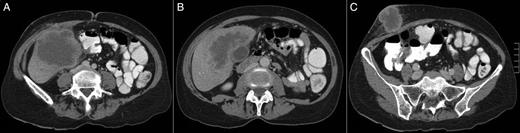

(A–C) A CT scan revealing a large hepatic mass invading the abdominal wall.